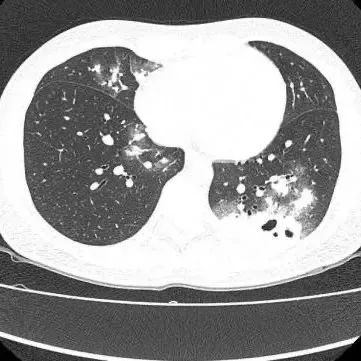

胸部CT显示其双肺多发感染

伴多发空洞形成

医生查房时,捕捉到CT上形似“鬼脸”的特殊影像(即“鬼脸征”),并伴有“晕伦征”,高度怀疑隐球菌肺炎。医生追问夏女士近期是否曾接触鸟类、禽类及饲养宠物,夏女士否认。

在影像学表现方面,典型CT表现是单发/多发结节伴“晕轮征”,结节液化坏死可形成空洞形似“鬼脸征”,空洞常为薄壁空洞、无液平。